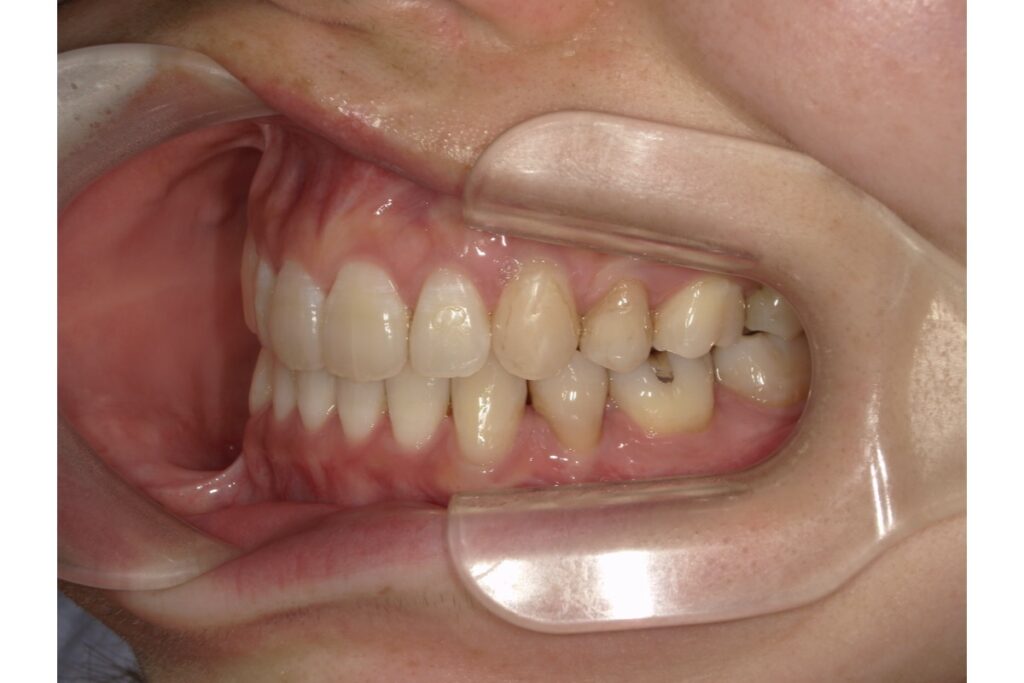

左下5番目の歯の治療前後の歯ぐきの位置を比較すると、歯茎が下がっているのがわかります。

「歯茎が下がる」とは、歯を支えている歯茎や骨が後退し、歯の根元が見えてしまう状態を指します。専門的には「歯肉退縮」と呼ばれ、以下のような見た目や症状が現れます。